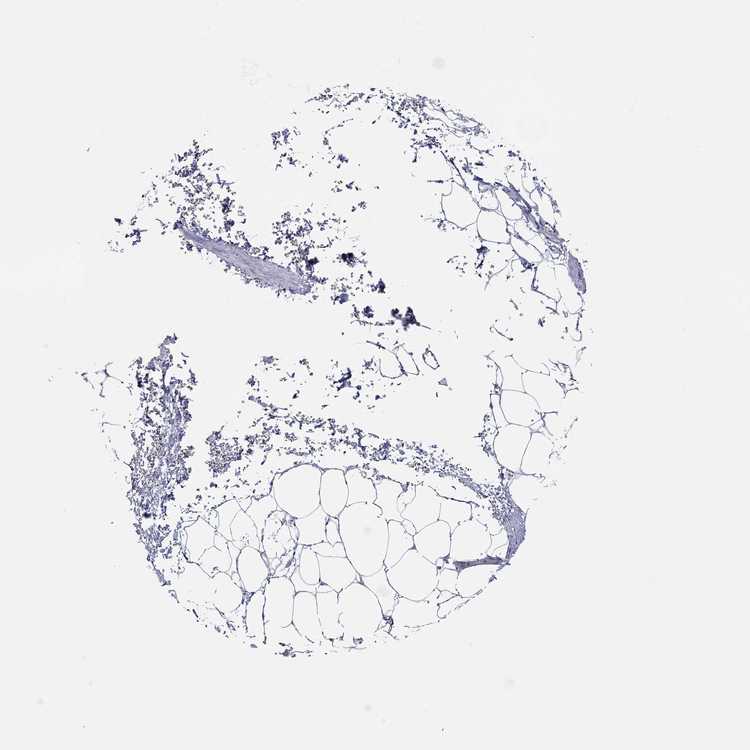

SOFT TISSUE 1 - Antibody stainingi

Antibody staining in the annotated cell types in the current human tissue is reported as not detected, low, medium, or high, based on conventional immunohistochemistry profiling in selected tissues. This score is based on the combination of the staining intensity and fraction of stained cells.

Each image is clickable and will lead to virtual microscopy that enables deeper exploration of all samples and also displays staining intensity scores, fraction scores and subcellular localization as well as patient and tissue information for each sample.

Antibody HPA075447

Fibroblasts Not detected

SOFT TISSUE 2 - Antibody stainingi

Peripheral nerve Not detected